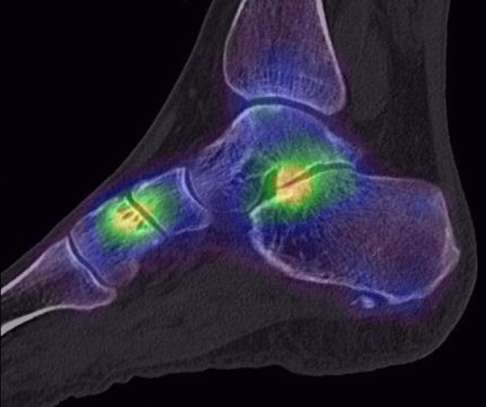

Bildgebende Diagnostik: Röntgen, DVT, MRT

Auf Röntgenbilder finden wir eindeutige Hinweise auf degenerative Veränderungen von Sprunggelenk und Fußgelenken. Unter Belastung – also im Stehen – können wir zudem eine Fehlstellung des Fersenbeines in mehreren Ebenen auf den Bildern zeigen. Des Weiteren untersuchen wir die Vorfußstellung im Verhältnis zum Rückfuß.

Das MRT-Bild (Magnetresonanztomografie) zeigt uns den Status von Sehnen, Bändern und Weichteilgeweben.

Mithilfe des DVT (digitale Volumentomografie) können wir einen Einblick in die genauen räumlichen Darstellungen der knöchernen Verhältnisse der beteiligten Fußknochen bekommen.